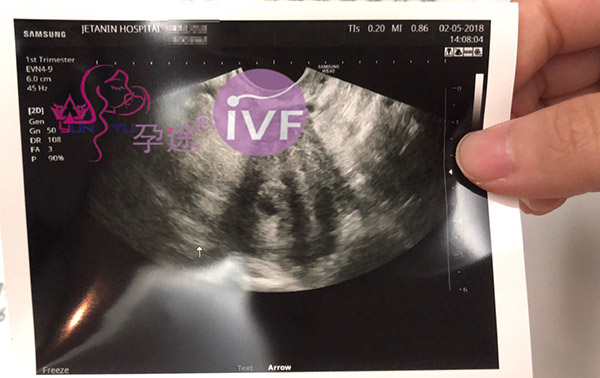

客户的男宝贝今天在杰特宁医院见诊YOKO医生B超看到孕囊!

客户的小男宝贝今天在杰特宁医院见诊YOKO医生B超看到孕囊了。客户高兴的说要跟YOKO医生合影留纪念!